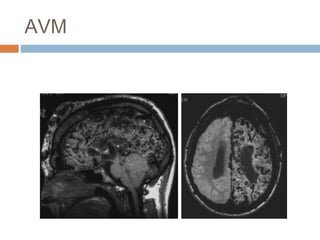

AVM: MRI

 Tín hiệu dòng chảy trống (flow

voids): “túi sâu”

 Xuất huyết: Nhòe hình trên GRE

 T2W: tăng tín hiệu Tăng sinh

thần kinh đệm (gliosis)

 Bắt thuốc mạnh

 MRA/MRV